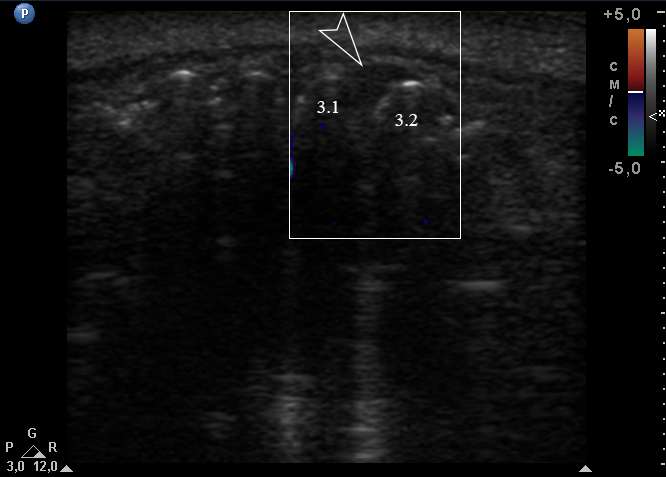

An extraoral ultrasound examination was performed by O.S.C., an expert physician (>18 years of experience in head and neck USG), on the day of admission in the department. A HD11 XE USG system (2007, the Philips, Amsterdam, the Netherlands) equipped with a linear L12-3 transducer (frequency fange: 3.0-12.0 MHz; aperture: 38 mm) was used for the examination, fixing a 3-cm of ultrasonography (penetration) depth.

Anterior part of the neoplasm at the vestibular aspect of the lower teeth measured 0.34 x 0.38 cm (Fig 3). Upon the gray-scale USG the anterior part portion of the neoplasm vizualized as homogenous hypoechoic lesion with no signs of calcifications. Color Doppler USG showed no vascularity within the vestibular portion of the neoplasm (Fig 4).